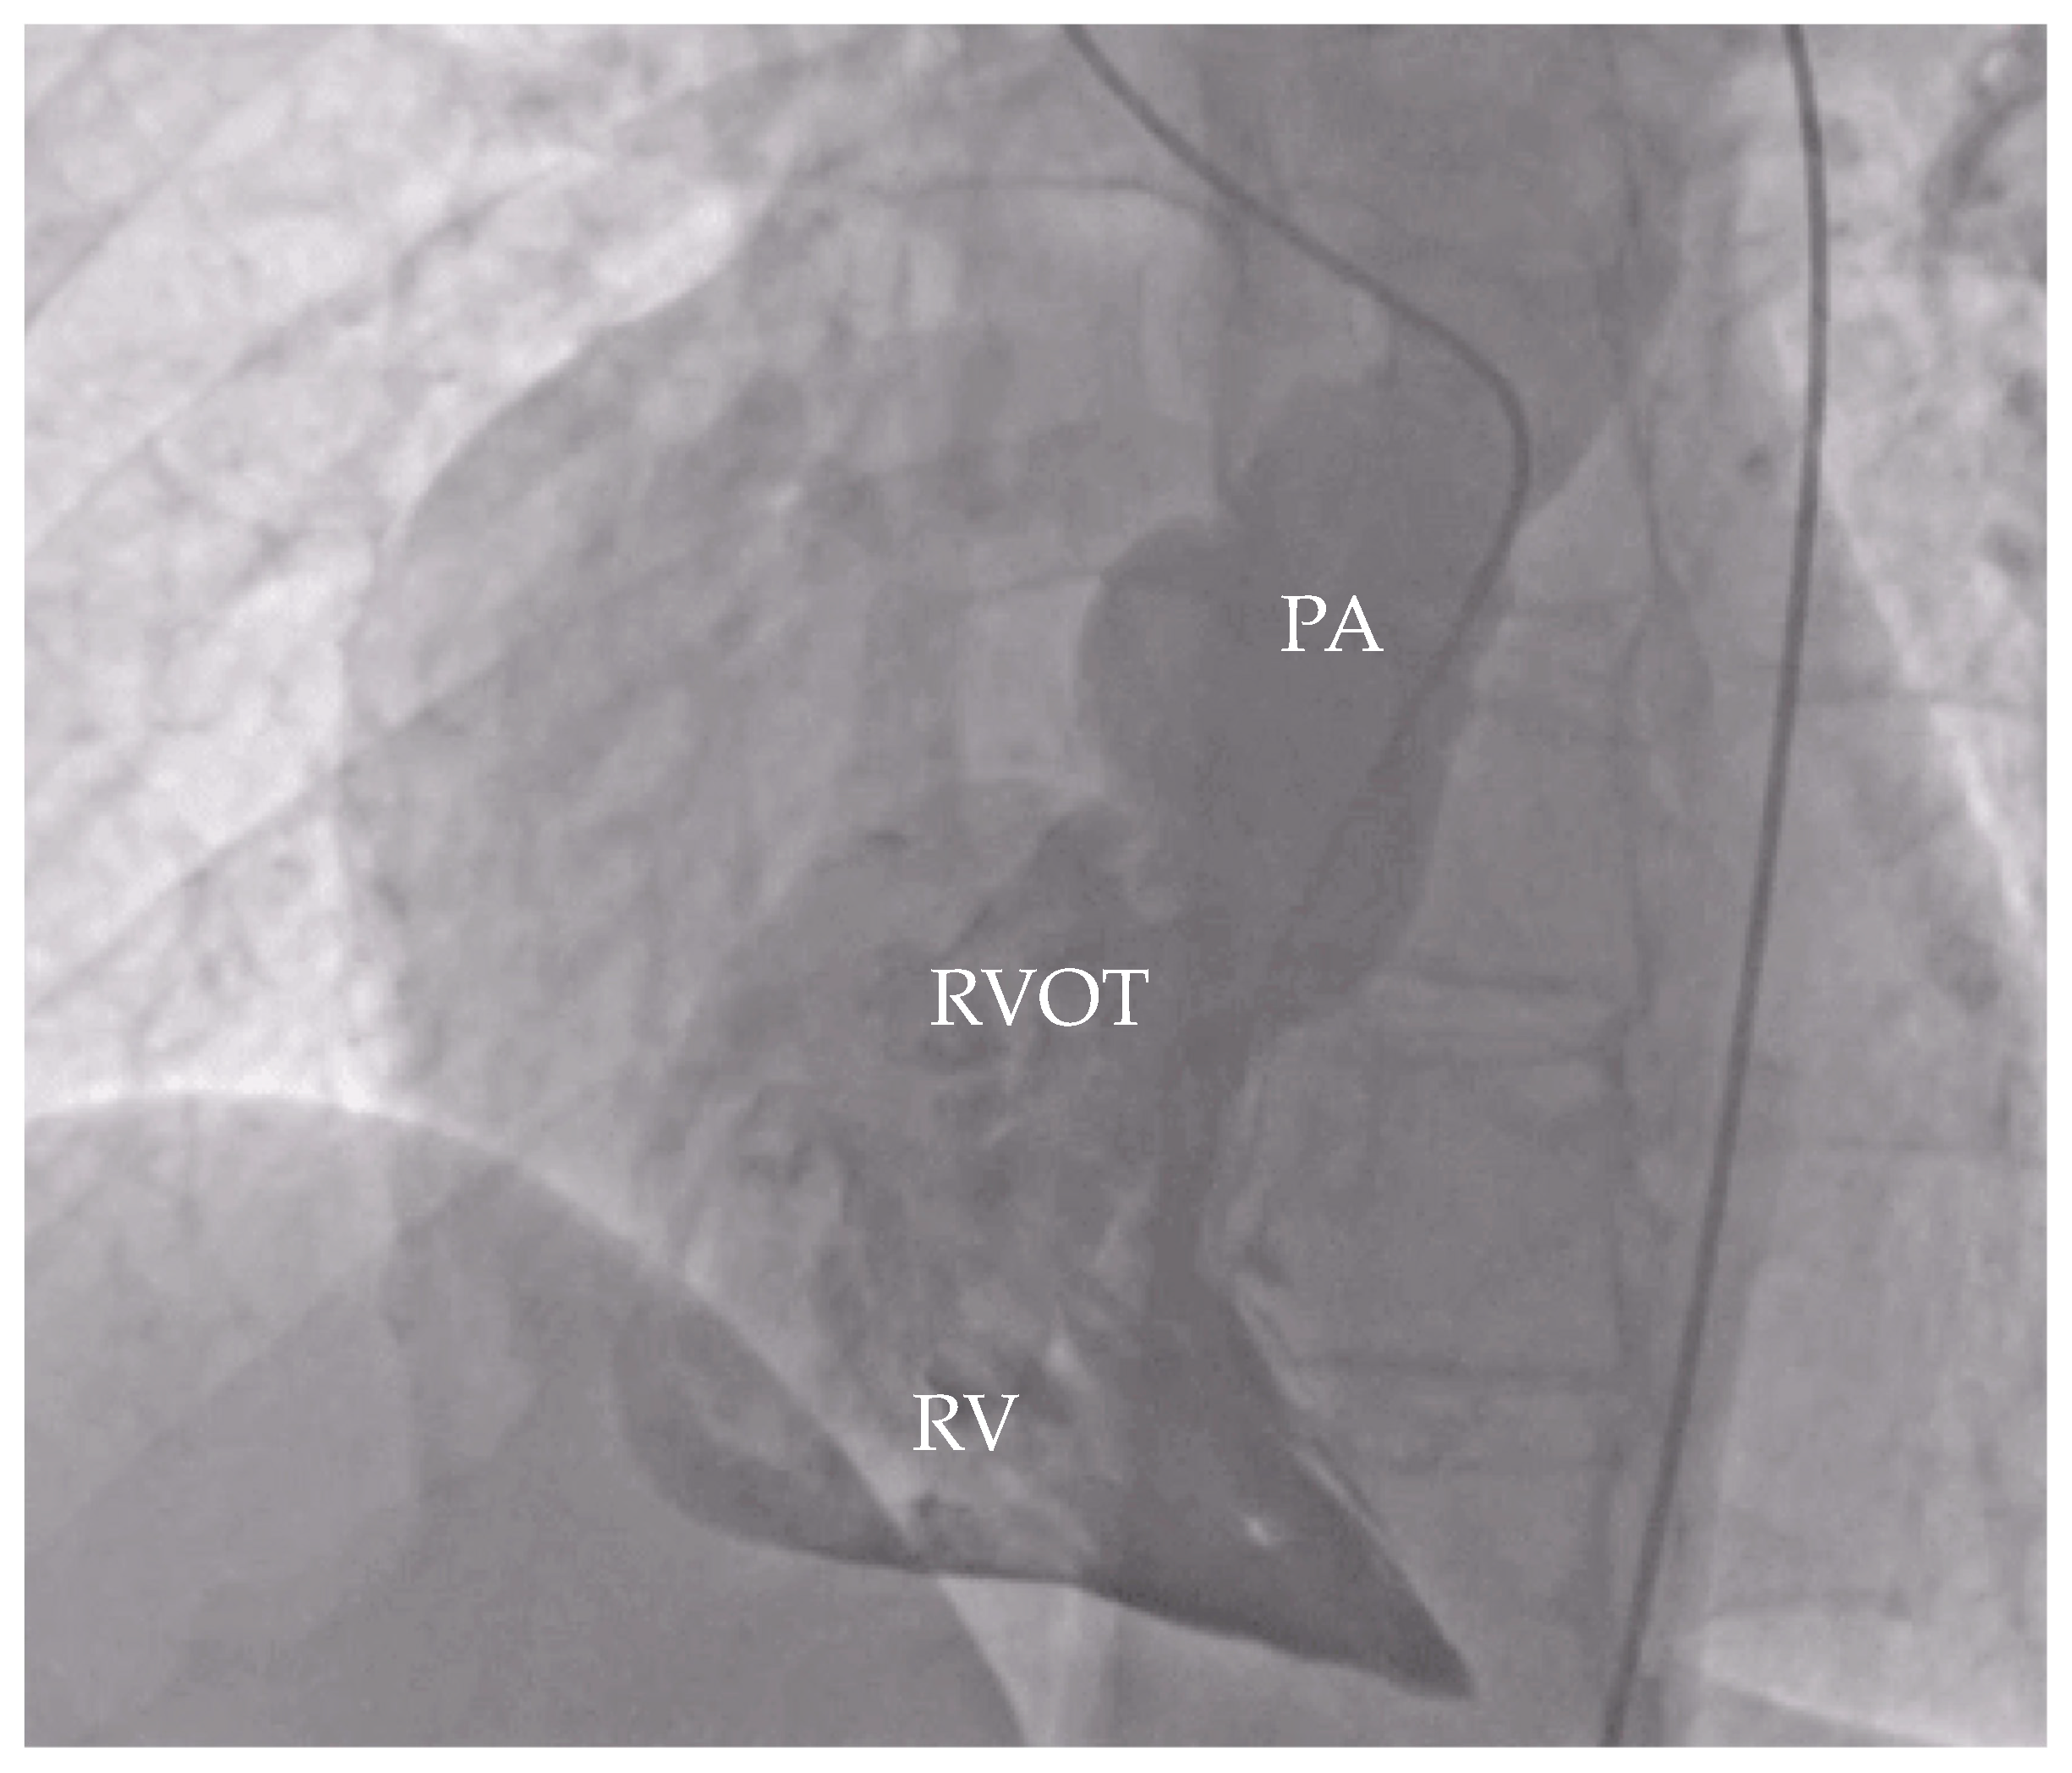

Transthoracic echocardiography (TTE) confirmed the diagnosis of a complete AVCD, with moderate to severe mitral regurgitation (MR) secondary to a cleft in the anterior mitral leaflet, a primum ASD, a ventricular septal defect, RV hypoplasia, and PS. Notably, apical displacement of the septal tricuspid leaflet by 19 mm and the presence of sail-like motion of the anterior tricuspid leaflet were highly suggestive of EA (Figure 1 and Figure 2).

Figure 1. Echocardiography with apical four-chamber view showing apical displacement of tricuspid septal leaflet. LV—left ventricle, LA—left atrium, RA—right atrium, ASD—atrial septal defect, SLD—septal leaflet displacement.